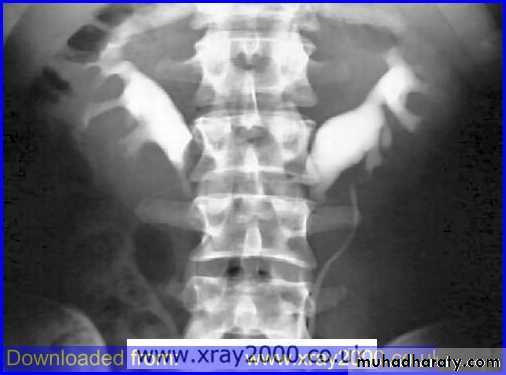

Horse shoe kidney :-*lower poles fused *low positioned kidneys *parallel to spines.*malrotated medially